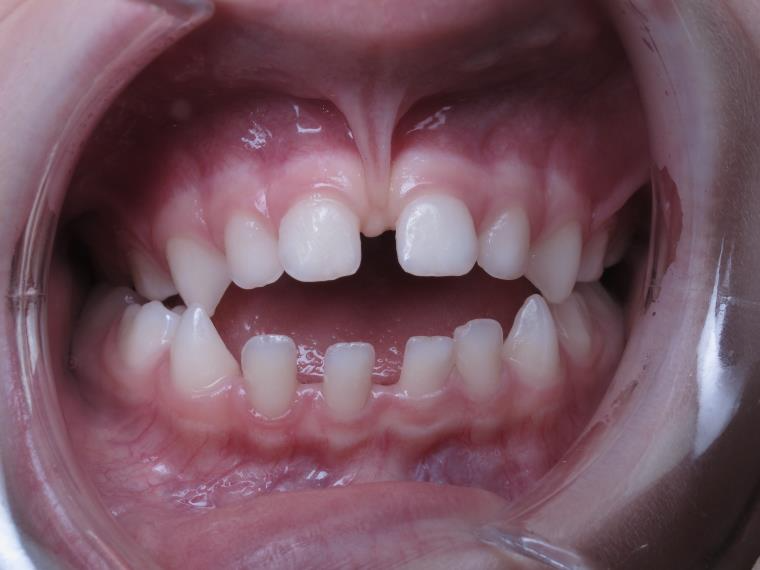

18 béance inversé droit 4 ans

inversion des dents postérieur et espace entre l'arcade du haut et du bas (béance)

bilan de début et en cours de traitement